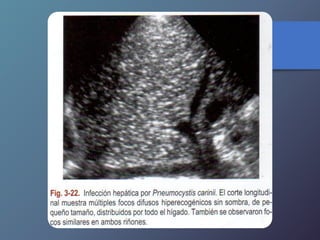

Infección Hepática Por

Pneumocistis Carinii

Es el microorganismo causal de

infección oportunista a pacientes con

inmunodeficiencia adquirida.

Van desde focos ecogénicos sin

sombras de pequeño tamaño hasta una

sustitución extensa del Parénquima

hepático.